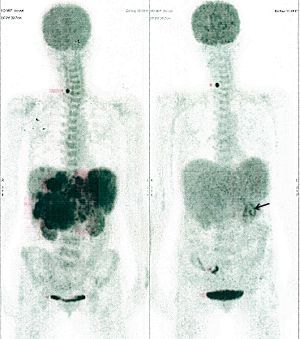

Below are some of the cases, from more than 80 cases we have treated so far with good results. When reading the PET/CT scans, the picture on the left is before treatment, and the picture on the right is after treatment. The intensity of black represents the activity of the cancer, but some black areas are not cancer: brain, heart, radioactive urine in bladder. For the heart, the intensity of black depends on the number of hours of fasting: if more than 10 hours, the heart is not even black, but if fasting is less than 6 hours, it is very black. The intensity of black in the brain can be variable in different scans depending on the brain activity at the time of the scan. The intensity of black in the radioactive urine can also be variable due to the hydration of patients and the time of injection of diuretic.

(HEPATOCELLULAR CARCINOMA + STOMACH CANCER)

A middle-aged women who is very thin and very weak, can hardly walk, lying in bed most of the time. She saw a cancer specialist in a top hospital who discovered that she had massive hepatocellular carcinoma, and another cancer in the stomach. Given that hepatocellular carcinoma is incurable and stomach cancer is very difficult if not impossible to cure without surgery, she was told that nothing could be done for her. She came to ask us to help her. After just 4 treatment, the hepatocellular carcinoma went into remission, and the stomach cancer (arrow) became less active. Until today, more than 6 months later, the hepatocellular carcinoma is still in remission.

CASE NO: 1 - A FEW MONTHS LATER

A few months after successful treatment for hepatocellular carcinoma, and partially successful for stomach cancer, the PET/CT scan showed the stomach cancer becoming very active, with several metastases to the parts of the liver not previously involved by hepatocellular carcinoma. After a few treatment, all the active stomach cancer lesions in the stomach and in the liver went into remission.